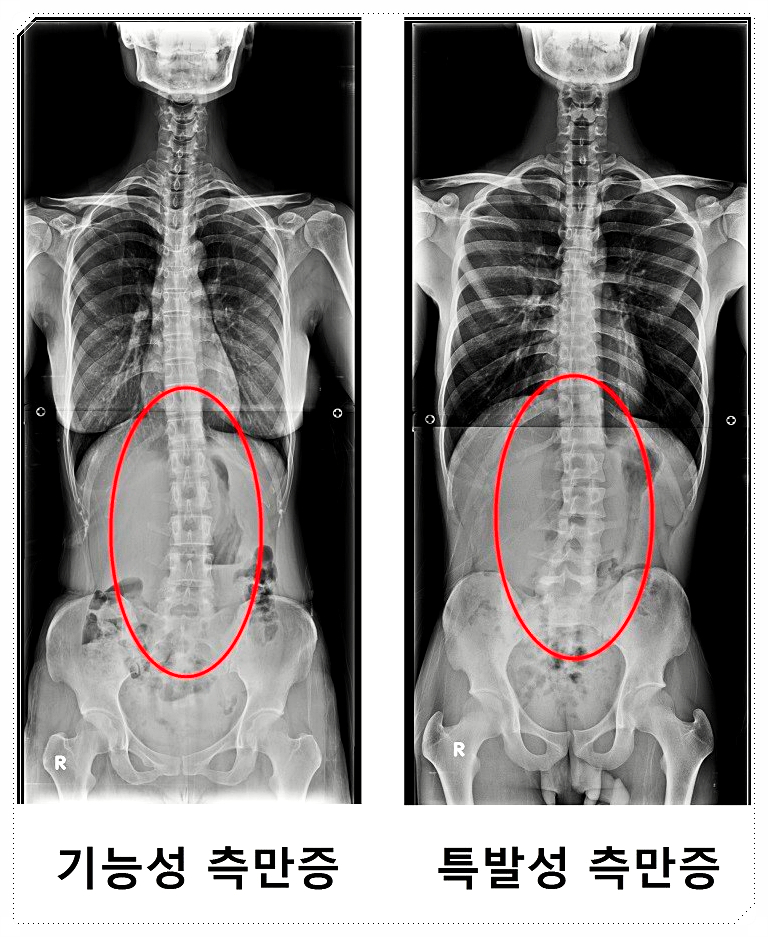

척추는 단순히 옆으로만 휘는 구조가 아닙니다.

사람마다 앞·뒤·옆으로 틀어지거나,

비틀리듯 꼬인 형태가 모두 다르게 나타나죠.

그래서 같은 ‘척추측만증’이라 하더라도

휘어진 각도와 방향, 회전 상태는 저마다 다른 양상을 보이게 됩니다.

이 때문에 척추의 변형은

평면적인 관점이 아닌, 3차원적인 구조로 이해하는 것이 중요합니다.